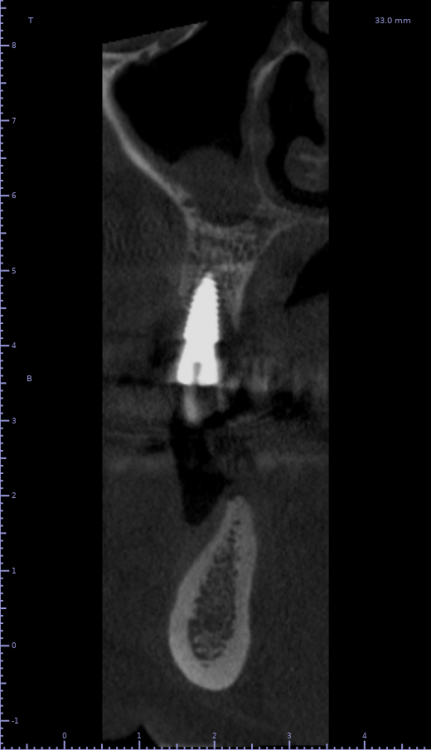

Женька Опубликовано 21 июля, 2021 Автор Поделиться Опубликовано 21 июля, 2021 3 месяца минуло... клык на торке 30 неприятные ощущения второй премоляр на 10 и подвижность... отправил на кт. Всё насмарку... Ссылка на комментарий

Борис80 Опубликовано 21 июля, 2021 Поделиться Опубликовано 21 июля, 2021 премоляр в любом случае недозаглубитом болеет... Ссылка на комментарий

Карен Аванесов Опубликовано 21 июля, 2021 Поделиться Опубликовано 21 июля, 2021 2 часа назад, Женька сказал: 3 месяца минуло... клык на торке 30 неприятные ощущения второй премоляр на 10 и подвижность... отправил на кт. Всё насмарку... Спишем на профессиональные вредности пациента курение и двухсот граммовые жимы на грудь , при переустановке, будет и легче и лучше. Гарантии какие были? Ссылка на комментарий

Irouil Опубликовано 21 июля, 2021 Поделиться Опубликовано 21 июля, 2021 1 час назад, Борис80 сказал: премоляр в любом случае недозаглубитом болеет... На момент установки не болел 3 часа назад, Женька сказал: Всё насмарку... Сочувствую Ссылка на комментарий